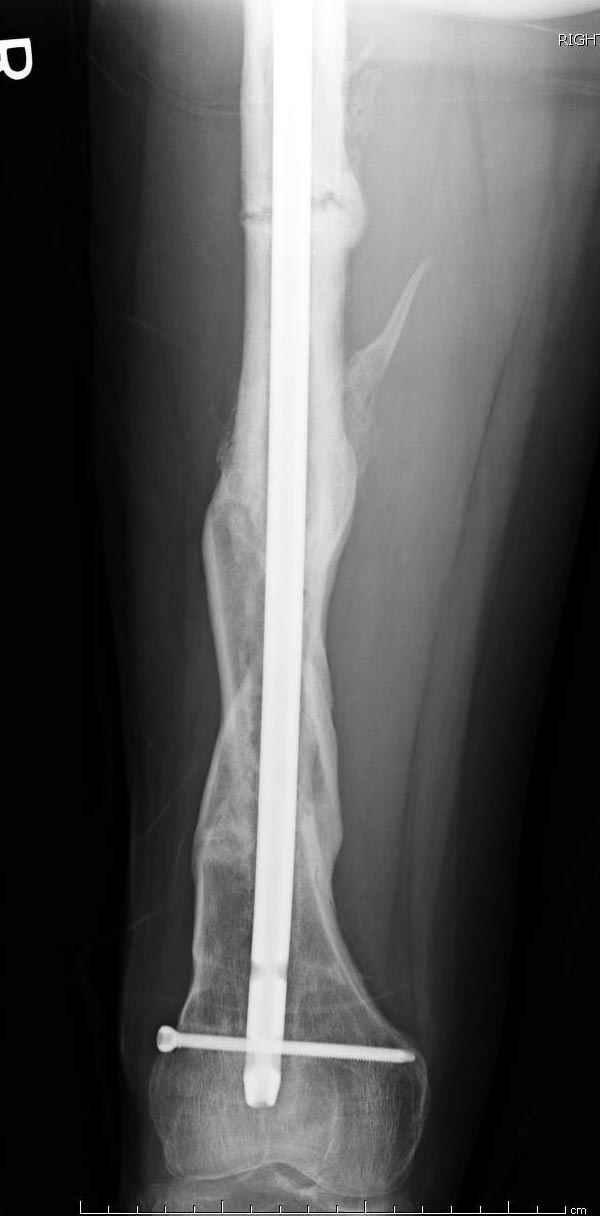

если первые 4 месяца послеоперационного периода проходил без проблем, но на 5 месяце появились боли в дистальном отделе бедра и температура, т.е. симптомы медуллярного инфицирования (рис №3, №4).

Замена реконструктивного штифта “Custom made Nail” с антибиотиком (рис №5, №6),

после промывки канала с рассверливанием внутреннего кортекса, через 4 недели антибиотический штифт удалили, оспалителный процесс остановлен и бедро сросся.